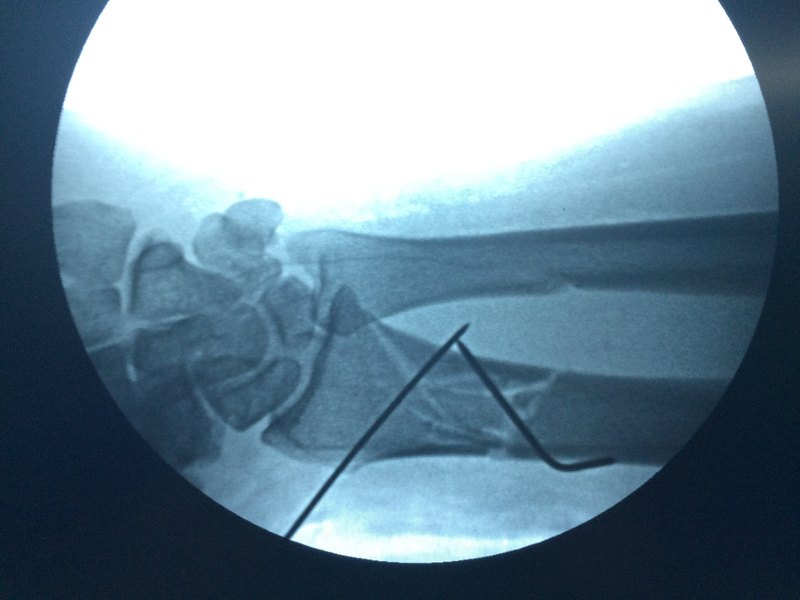

毛里提拜克·托里根? 副主任醫(yī)師? 昌吉州人民醫(yī)院? 骨一科1107人已讀 - 還在苦惱醫(yī)生反復(fù)說你的片子不清楚么?我教你正確的方法

各位如需要把影像資料發(fā)給你的醫(yī)生朋友,請這樣做,這樣我們可以清楚的閱片。 【 X線片、MRI 膠片拍照 】 上傳影像學(xué)資料的辦法: 【 第一種 】 將自己家的電視頻幕調(diào)成一素的白底色,再將膠片放在屏幕上,拍照(不用閃光燈),傳送。 對于CT, MRI 拍照時,應(yīng)該選擇性分4~6塊拍照,避免眉毛胡子一把抓。 且,不用閃光燈。 【 第二種 】 打開電視、電腦,將屏幕桌面設(shè)置白色,然后將X線、MRI 或 CT片子夾在桌面上,產(chǎn)生閱片燈箱的效果。 不用閃光燈拍攝,不用閃光燈拍照的效果特別最好! 電腦桌面怎樣可以設(shè)置成白色的方法可以點擊以下網(wǎng)址: http://jingyan.baidu.com/m/article/11c17a2c6dd978f447e39d53.html 【 第三種 】 在醫(yī)院燈箱上,放置膠片,拍照(不用閃光燈),傳送。 發(fā)圖片時,為了保持像素,在選擇完圖片后,點預(yù)覽鍵,按原圖發(fā)送,再發(fā)送,不失真。 千萬避免直接發(fā)送,不然清晰的全真圖片就發(fā)不出來了。 按我說的,新技術(shù),原像素上傳的,清晰的圖片如下:

毛里提拜克·托里根? 副主任醫(yī)師? 昌吉州人民醫(yī)院? 骨一科1450人已讀